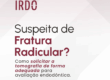

Porém, ao realizarmos a navegação de maneira adequada, associando os 3 planos e trabalhando escala de cinza, foi possível localizar e diferenciar um canal lateral nesta região (imagens 3,4 e 5), e que, não por coincidência, sua saída está localizada no epicentro da reabsorção óssea.

Canal lateral visível nos três planos

O diagnóstico só foi possível com navegação detalhada e uso correto da escala de cinza.

Saída do conduto lateral coincide com a área de reabsorção óssea